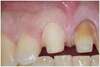

CAS ESTHÉTIQUE ANTÉRIEUR POUR 2 INCISIVES CENTRALES

Le patient se présente avec des anciennes reconstitutions antérieures inesthétiques suite à un choc.

La teinte est prise, des préparations périphériques sont réalisées et des provisoires de laboratoire sont mises en place pendant 15 jours.

Les couronnes sont descellées, les couronnes essayées et posées définitivement. Nous notons la qualité de la gencive. Le patient est très satisfait.